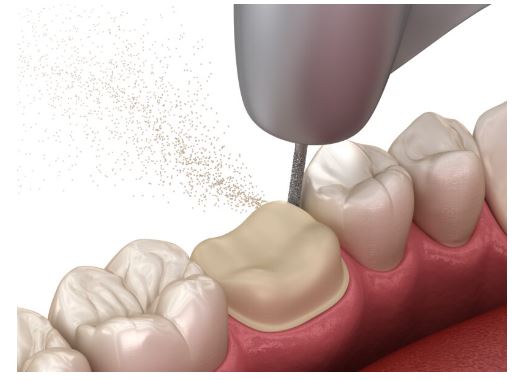

먼저 프렙해주는 과정을 가졌습니다.

이때 보철이 들어갈 두께랑

들어가는 각도를 생각하면서

다듬어줘야 됩니다.

신대방 치과는 세세한 과정도

꼼꼼하게 하고 있습니다.

이런 과정을 거쳐 인상채득을 하여

자체 기공실에서 정밀한 크라운을 제작하였습니다.